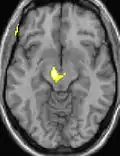

| La tomographie par émission de positons (TEP) montre les zones du cerveau étant activées durant la douleur | ||

| La morphométrie voxel par voxel (VBM) montre les différences structurelles des zones du cerveau | ||

Les images par tomographie à émission de positron indiquent les régions du cerveau qui sont activées lors de la douleur, par rapport aux périodes sans douleur. Elles montrent les régions du cerveau qui sont toujours actives durant la douleur en jaune/orange (appelé "matrice-douleur"). La zone au centre (dans les trois vues) est spécifiquement activée uniquement pendant la crise. Les photos sur la ligne du bas (effectuées par VBM) montrent les différences structurelles entre les patients souffrant d'AVF et des personnes saines : seulement une partie de l'hypothalamus est différente[50],[51].